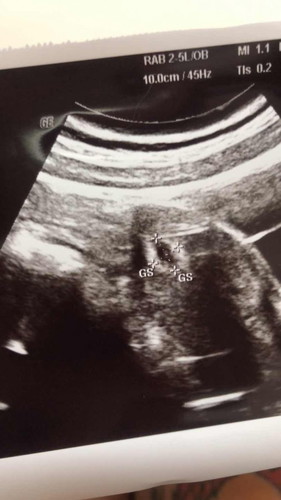

ใบอันตร้าซาว

แม่ๆไปซาวครั้งแรก เป็นแบบนี้ไหมคะ ขอบคุณสำหรับคำตอบค่ะ

บ้านนี้ ซาวค์ตอน 5w เห็นแค่นี้เองคะ ตอนนี้ 28w แล้วค่ะ

ช่วงแรกเห็นแค่นี้แหละค่ะ เล็กจิ๋วเท่าเม็ดถั่ว

แบบนี้ค่ะ เห็นแต่ถุง